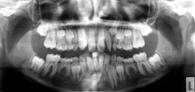

| Fernröntgenbild | Orthopantomogramm |